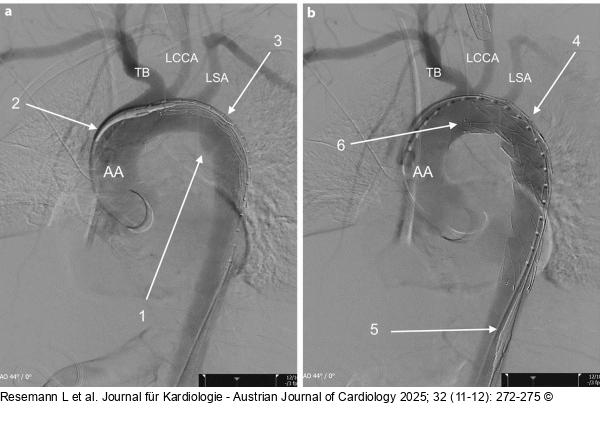

Abbildung 2: Angiegraphie 2a: Subtraktionsangiographie vor Absetzen des Stentgrafts: AA – Aorta ascendens; TB – Tr. brachiocephalicus; LCCA – A. carotis communis sinistra; LSA – A. subclavia sinistra; 1 – Pseudoaneurysma; 2 – Spitze des Stentgraftapplikators; 3 – noch nicht expandierter Stent; 2b: Subtraktionsangiographie nach abgesetztem Stentgraft: 4 – freigesetzter Stent, das Pseudoaneurysma ist von der Perfusion exkludiert; 5 – zurückgezogene Spitze des Stentgraftapplikators; 6 – proximales Stentende unmittelbar nach Abgang der LCCA |

2a: Subtraktionsangiographie vor Absetzen des Stentgrafts: AA – Aorta ascendens; TB – Tr. brachiocephalicus; LCCA – A. carotis communis sinistra; LSA – A. subclavia sinistra; 1 – Pseudoaneurysma; 2 – Spitze des Stentgraftapplikators; 3 – noch nicht expandierter Stent; 2b: Subtraktionsangiographie nach abgesetztem Stentgraft: 4 – freigesetzter Stent, das Pseudoaneurysma ist von der Perfusion exkludiert; 5 – zurückgezogene Spitze des Stentgraftapplikators; 6 – proximales Stentende unmittelbar nach Abgang der LCCA |